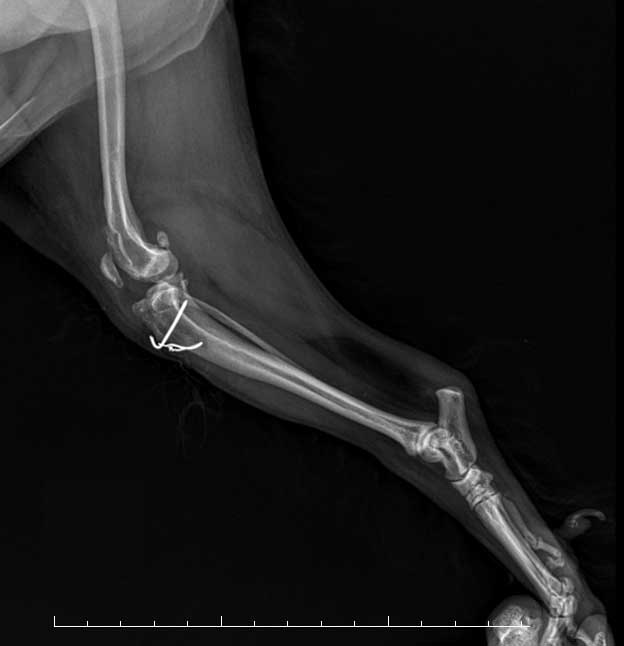

• X-ray 검사 이미지

02

X-ray 검사

무릎 관절을 체크하고,십자인대 단열을 확인합니다.

• 노령견 십자인대 수술 이미지

ECS 노령견 십자인대 수술

기저 질환을 가지고 있는 노령견,

안정성을 더한 맞춤 수술 케이스